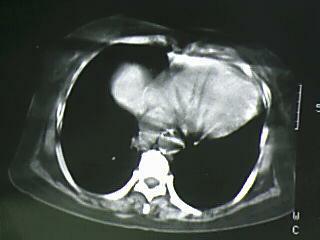

以下是引用bmw011在2009-4-14 19:14:00的发言:[br]右肺继发型肺结核---纵隔淋巴结多发钙化----左肺支扩。支持

以下是引用杀毒软件在2009-4-14 17:52:00的发言:[br]考虑---右肺继发型肺结核---纵隔淋巴结多发钙化----左肺支扩

以下是引用黑白光影在2009-4-14 20:36:00的发言:[br]右肺继发型肺结核;左下慢性支气管炎性病变。